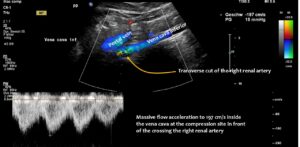

However, functional colour Doppler ultrasound revealed that the problems were caused by compression of the inferior vena cava. The patient’s increased lumbar lordosis, resulting from a connective tissue disorder (hypermobile Ehlers-Danlos syndrome), pushed the inferior vena cava ventrally.

The upper lumbar vertebrae thus acted as a barrier against which the expanding duodenum pressed the vena cava. The situation was exacerbated by the duodenum not functioning properly, causing food to become lodged in the descending portion of the duodenum, directly in front of the inferior vena cava.

When the patient stood up, gravity pulled the liver downwards.

Due to the lax connective tissue, the liver was less fixed and thus developed orthostatic hepatoptosis, sliding down like a sled on a ramp — the cranial slope of the lumbar lordotic curvature — while standing. This compression was exacerbated by the perpendicular crossing of the right renal artery, which runs behind the vena cava and in front of the lumbar spine, acting as a bar and making the compression even more efficient.